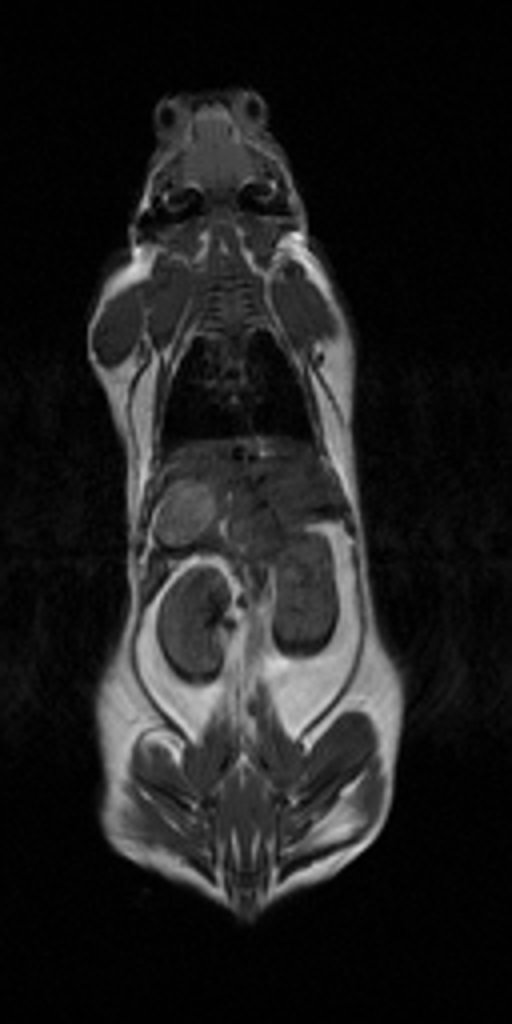

Ejemplos de refinamiento incluyen el realizar técnicas de anestesia sofisticadas, similares a las empleadas en personas en un hospital o en animales en un centro veterinario, así como el empleo de técnicas quirúrgicas avanzadas como las de laparoscopia, igualmente similares a las empleadas en medicina humana y veterinaria.